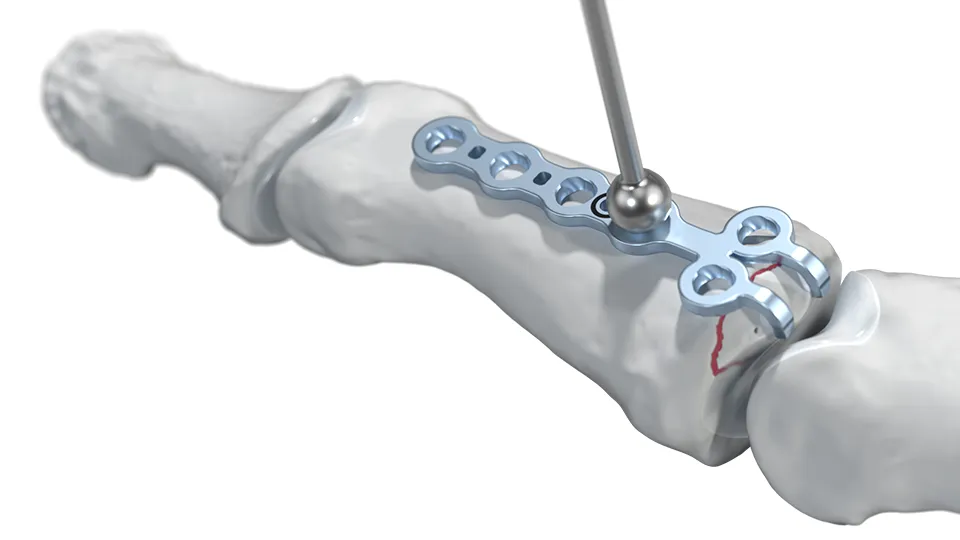

El Sistema 1.5 para cirugía de mano está diseñado para ofrecer fijación estable y precisa en procedimientos de traumatología y reconstrucción. Fabricado con materiales de alta calidad, garantiza biocompatibilidad, resistencia y un óptimo desempeño funcional quirúrgico, permitiendo una recuperación segura y eficiente para el paciente.